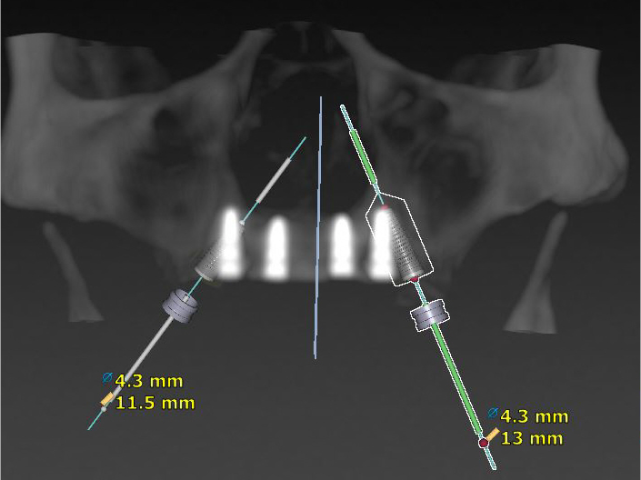

While the ideal position and size of your teeth are designed on specialised ‘bite and smile design’ software, your surgery can be planned on specialised surgical planning software. A CT scan is obtained and loaded into the planning software to allow Dr. Currie to plan the appropriate number and size of dental implants for your surgery.